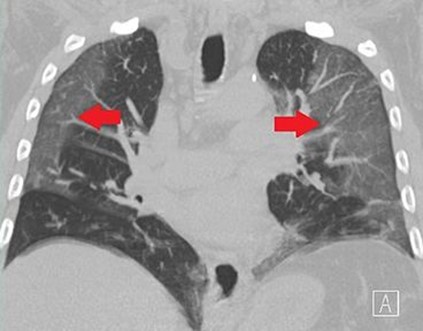

“Bệnh phổi trắng” hay “hội chứng phổi trắng” chỉ là một cách một mô tả đơn giản “đáng sợ”, không được các chuyên gia y tế sử dụng, nhưng từ “white out “ được bác sĩ quang tuyến dùng để mô tả những gì chúng ta thấy trên phim chụp X-quang ngực thông thường hay CT phổi. Phổi khỏe mạnh chứa đầy không khí và để cho tia X đi xuyên qua dễ dàng nên trên phim X quang những vùng này sẽ màu đen (radiolucent), khi tình trạng viêm phổi, và các tế bào bạch cầu lấp đầy khu vực vị nhiễm trùng, phổi sẽ cản tia X nhiều hơn (radio-opaque), hình trên phim trở nên mờ đục và có màu trắng hơn. Trước đây, những người bị lao phổi (viêm phổi do vi trùng lao) thường được gọi là “nám phổi” vì một phần của phổi có hình “nám” hay đục (opaque) trên hình quang tuyến. Một phần hoặc toàn bộ lá phổi bị trắng có thể xảy ra:

-”ground glass appearance”; hình mờ đục như kính nhám do bắn cát vào (sand blasted glass) là một cách các bác sĩ quang tuyến mô tả các vùng màu xám mờ có thể hiển thị trong ảnh chụp X-quang hay CT phổi. Những khu vực này cho thấy mật độ bên trong phổi tăng lên (increased density) có thể chỉ ra bệnh viêm phổi hoặc các rối loạn hô hấp khác. Có một số tin từ Trung Quốc cho thấy những hình phổi loại này.